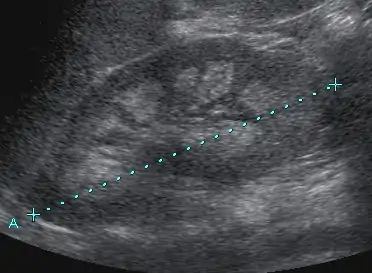

Medullary nephrocalcinosis in Sonography

Nephrocalcinosis is diagnosed for the most part by imaging techniques. The imagings used are ultrasound (US), abdominal plain film and CT imaging.[11] Of the 3 techniques CT and US are the more preferred. Nephrocalcinosis is considered present if at least two radiologists make the diagnosis on US and/or CT. In some cases a renal biopsy is done instead if imaging is not enough to confirm nephrocalcinosis. Once the diagnosis is confirmed additional testing is needed to find the underlying cause because the underlying condition may require treatment for reasons independent of nephrocalcinosis.[11] These additional tests will measure serum, electrolytes, calcium, and phosphate, and the urine pH.[11] If no underlying cause can be found then urine collection should be done for 24 hours and measurements of the excretion of calcium, phosphate, oxalate, citrate, and creatinine are looked at.[11]